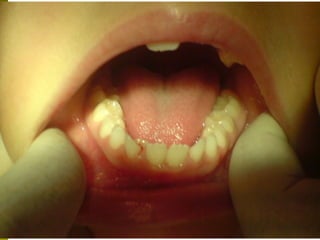

Πρώτη σχολική ηλικία 6-10 ετών

   Αρχίζει αλλαγή των τομέων και η ανατολή των

πρώτων μόνιμων γομφίων (μεικτή οδοντοφυΐα)

   Παρατηρούμε η αλλαγή δοντιών να γίνεται με τη

σωστή σειρά και στη σωστή θέση

   Μπορεί να χρειαστεί πρώιμη ορθοδοντική

θεραπεία, για να αποφευχθούν πιο δύσκολες και

πολύπλοκες εργασίες αργότερα

   Διατήρηση νεογιλών δοντιών στον οδοντικό

φραγμό μέχρι τη φυσιολογική τους απόπτωση